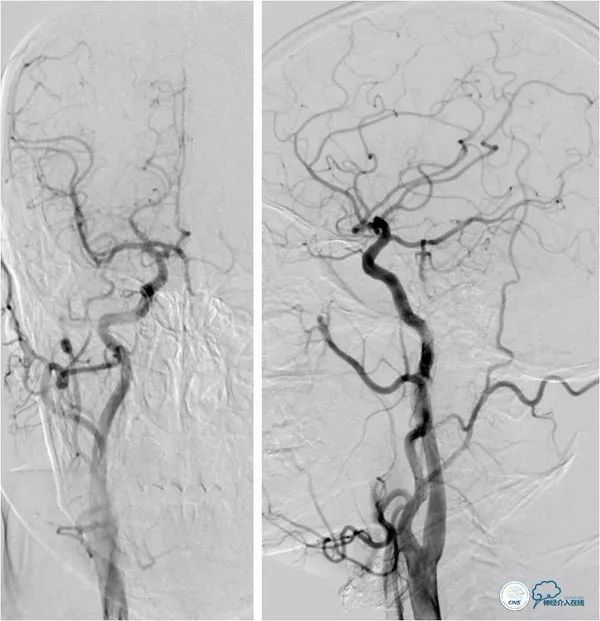

DSA:双侧颈动脉系统未见异常,双侧后交通动脉开放,右颈动脉造影可见基底动脉中上段显影。左椎动脉闭塞,右椎动脉V4段重度狭窄,基底动脉中段偏心重度狭窄(图5-8)。

图5

图6

图7

图8